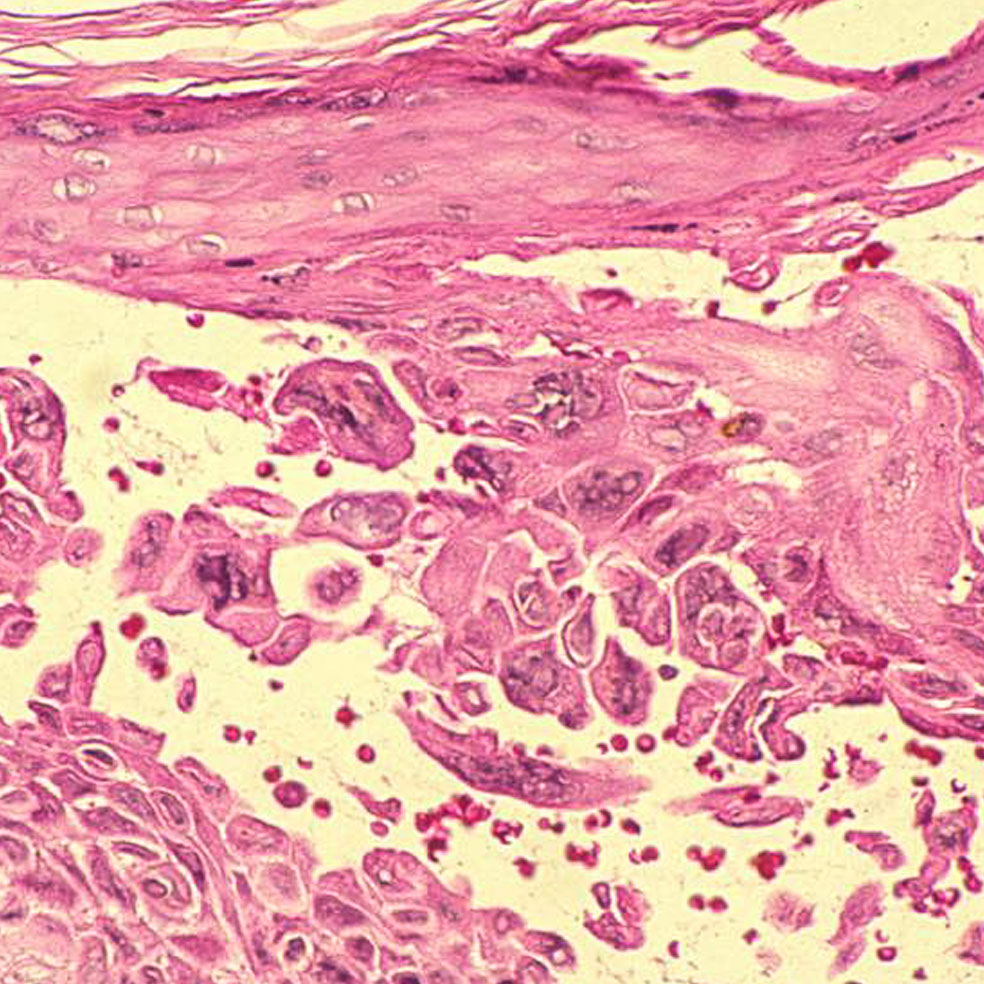

El origen se halla en tres tipos de hongos: Microsporum, Epidermophyton y Trichophyton, criaturas milenarias que invaden las capas superficiales de la piel, el pelo y las uñas. Es donde encuentran alimento y se reproducen. Por eso una vez ahí se multiplican, generando una erupción cutánea redondeada que se deshace en escamas y causa picor. Si no se trata a tiempo, puede provocar dolor, fiebre, caída del cabello e, incluso, alopecia en las zonas afectadas. Su capacidad de transmisión es muy elevada: basta tocar a una persona infectada u objetos contaminados como las máquinas en cuestión, peines, ropa, suelo de duchas, piscinas...

7. Tiña podal: Dando pie a la infección

Trichophyton y Epidermophyton son dos géneros de hongos que se pegan a los pies en las duchas públicas, ocasionando una infección conocida como tiña podal o pie de atleta. Estos microorganismos proliferan en zonas cálidas y húmedas, por lo que se recomienda tener los pies limpios y secos, sobre todo entre los dedos.